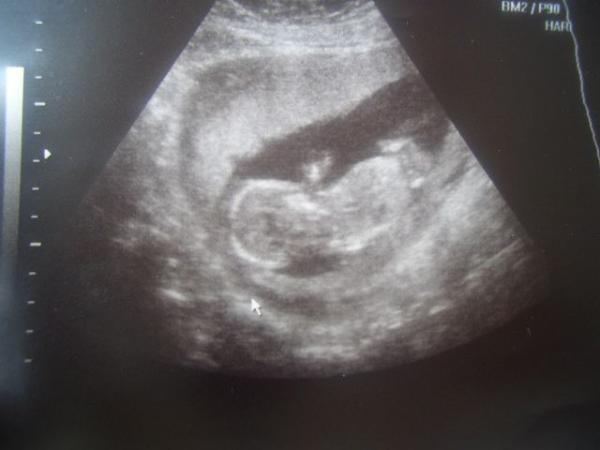

das ist aus der 12 SSW

Bild zu Zwei Ultraschallbilder euch zeigen möchte.... - Forum für März - Mamis